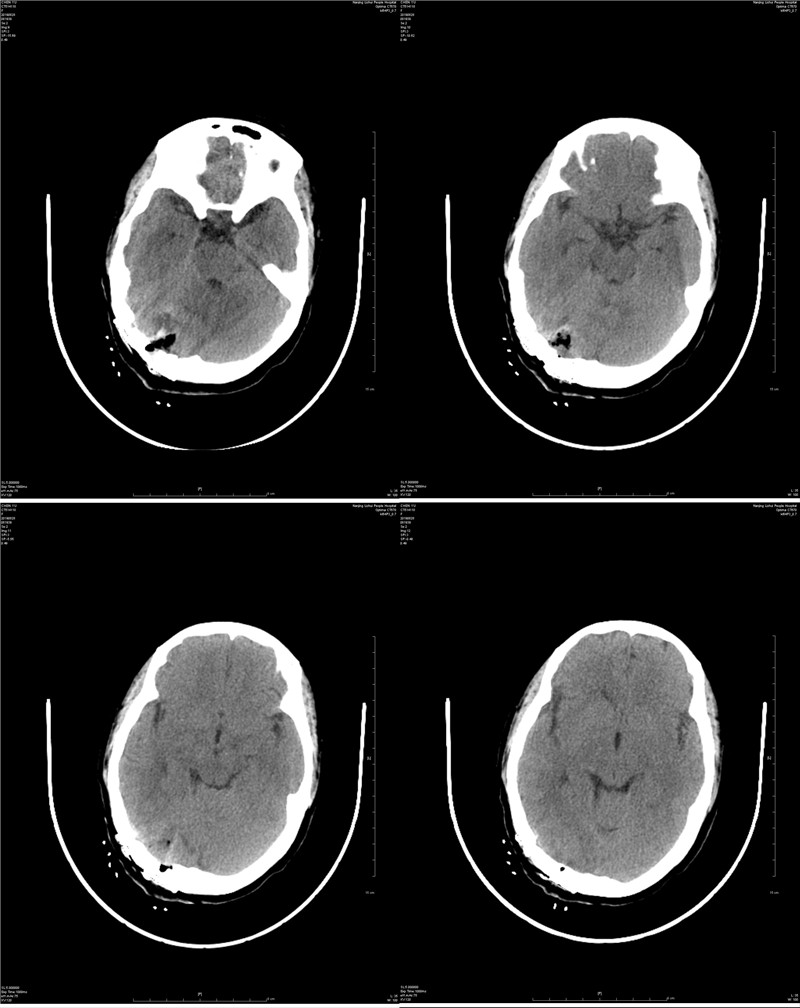

近日,神经外科收治了一例后颅窝跨天幕脑膜瘤的患者,经手术治疗后患者痊愈出院。这是我院独立完成的首例后颅窝脑膜瘤切除术,术后患者恢复良好,无手术并发症,这标志着神经外科在颅内肿瘤显微手术技术上又迈上一个新的台阶。 后颅窝是颅腔的一个特殊部位,有众多重要血管和神经穿行其中。此外,与幕上颅腔相比,后颅窝空间狭小,却容纳有脑干、小脑半球及除Ⅰ、Ⅱ神经外的所有颅神经,常因手术显露牵拉脑组织、术后脑水肿,造成严重后果,长期以来一直是神经外科手术的难题之一。 该患者一年多来偶有头疼头晕症状,经体检后发现颅内有一蛋黄大小肿瘤。患者家庭经济条件一般,子女尚未成家,面对一笔不小的手术费用深表担忧。床位医生周立田副主任医师对患者及家属耐心讲解,表示尽可能的控制住院诊疗费用,患者及家属终于打消了顾虑并决定在我院手术治疗。 经过缜密讨论研究,术前精心设计了手术方案,由神经外科杨平来主任医师、周立田副主任医师联手主刀,经过近6个小时不懈的努力和精细的操作,显微镜下成功全切肿瘤,并完整地保留了肿瘤压迫的重要引流静脉,手术取得圆满成功。 此例手术的成功开展,得益于神经外科团队技术的不断提升,神经外科将以此为动力,以精湛的医疗技术、最低的治疗费用和优质的医疗服务为溧水百姓的健康保驾护航!